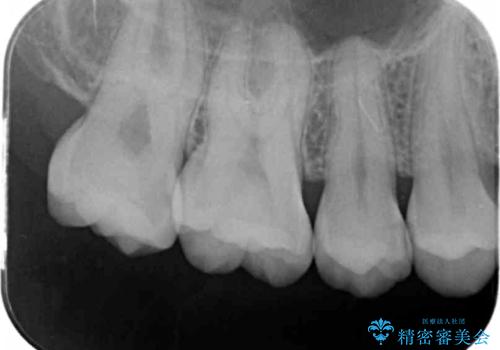

- 検査の結果左上の歯と歯の間に虫歯が発見された患者様です。

虫歯の除去後セラミックインレーでの修復処置をしていきます。

歯と歯の間は虫歯の好発部位とされています。

適合の良いインレーでの修復をすることで再発を防止します。